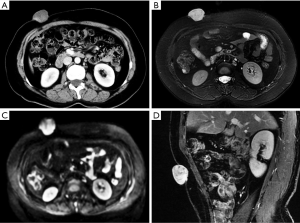

Hematomas

Anterior abdominal wall hematomas usually occur in the rectus abdominis muscle and result from damage, such as a trauma or surgical intervention, to the superior or inferior epigastric arteries or direct tearing of the rectus muscle. Other uncommon reasons are clotting deficiency or anticoagulant treatment. Hematomas in the absence of trauma or after light trauma are usually difficult to distinguish from tumors with hemorrhage in clinical practice, and contrast-enhanced MRI will facilitate the differential diagnosis (64).

Hematomas present as well-defined, hyperdense rectus masses on unenhanced CT and may show active contrast extravasation on enhanced CT. Their appearance on MRI depends on the stage of the hemorrhage. Deoxyhemoglobin in the acute stage manifests as iso- or hypointense areas on T1WI and T2WI. Methemoglobin in the subacute stage often produces high SI in the form of a peripheral rim, which is a very useful diagnostic factor (Figure 14). In the chronic phase, the dark hemosiderin rim on T1WI and T2WI is a useful discriminating feature (1). CT and MRI help achieve an accurate diagnosis and can be used to evaluate the extent of a hematoma and the presence of active bleeding (3).